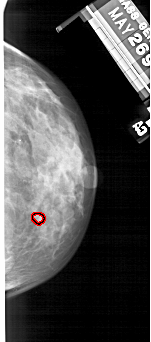

FILE: A_1497_1.RIGHT_MLO.OVERLAY

TOTAL_ABNORMALITIES 1

ABNORMALITY 1

LESION_TYPE CALCIFICATION TYPE PLEOMORPHIC DISTRIBUTION CLUSTERED

ASSESSMENT 4

SUBTLETY 2

PATHOLOGY BENIGN

TOTAL_OUTLINES 1

BOUNDARY